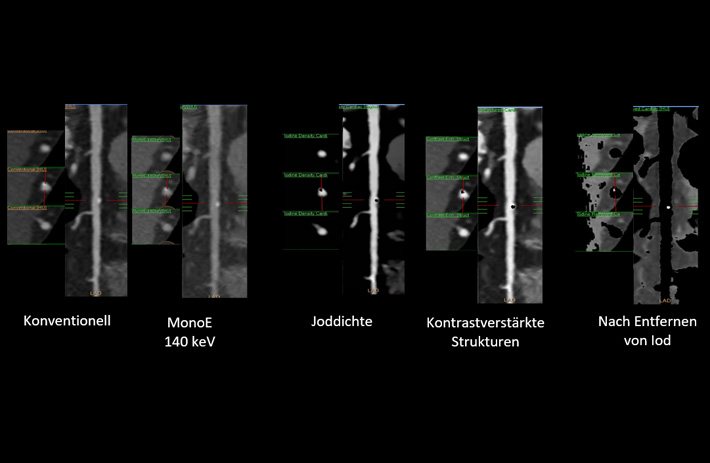

Mit dem Spektral-Detektor-CT werden Spektraldaten automatisch bei jedem Scan erfasst. Die Informationen stehen jederzeit auf der Scankonsole, der CT-Workstation sowie an jedem PACS-Arbeitsplatz zur Verfügung, sodass es nicht notwendig ist, den Patienten erneut zu scannen, bspw. wenn initial zufällige Anomalien festgestellt wurden. Dadurch profitieren Anwender durch eine höhere Diagnosesicherheit und weniger Nachuntersuchungen auf anderen bildgebenden Systemen. Unsere Fallsammlung zeigt, welchen klinischen Mehrwert der Spektral-Detektor-CT in unterschiedlichsten Anwendungsbereichen in der klinischen Routine bringt. Jede Woche gehen neue Fälle live.